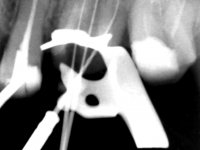

Male patient, 34 years old, non-smoker. Teeth 17 and 16 had extensive restorations with composite resin and placed intra-radicular posts. In the imaging examination, it was found that the endodontic treatment was not technically satisfactory, but had been asymptomatic for several years. The patient was rehabilitated with a 2-element bridge at 17 and 16 and 4 years later an abscess appeared in the apical area of 2.6. It had the 2.8 tooth included with a close relationship with the 2.7 root. During these 4 years there was no positional change of this tooth. After endodontic retreatment of teeth 27 and 26, an abscess appears again in the area of tooth 26, possibly associated with a root fracture. Given the history referred to in relation to tooth 26, it was considered a tooth with indicated extraction.

Teeth 17 and 16 were prepared for the fabrication of a 2-element Zr bridge. The impression was performed with a double mixing technique and a monolithic bridge in Zr was made in the laboratory. 4 years later, an abscess appeared in the apical area of tooth 26. It was decided to remove the bridge, remove the intra-radicular posts and retract the endodontic treatments of teeth 17 and 16. The removal of the bridge was carried out by making two cervical cavities. in the palatal area of the bridge and with a microluxator, disinsertion movements were performed. The intra-radicular posts were removed using fine drills and an ultrasound tip. The bridge was provisionally cemented and the patient was referred to a fellow endodontist for endodontic retreatment. After the retreatment, the intraradicular posts were placed again and the bridge was definitively cemented. One year later, a new abscess appears, possibly related to a root fracture. The bridge was sectioned between tooth 27 and 26 and tooth 26 was extracted and the crown of 27 was provisionally cemented. 3 months later, teeth 27 and 25 were prepared and a temporary bridge was made in dual polymerization resin. Then, an impression was made using the double mixing technique and a 3-element bridge in Zr was made in the laboratory. It was permanently cemented in the mouth with resin-reinforced glass ionomer cement.